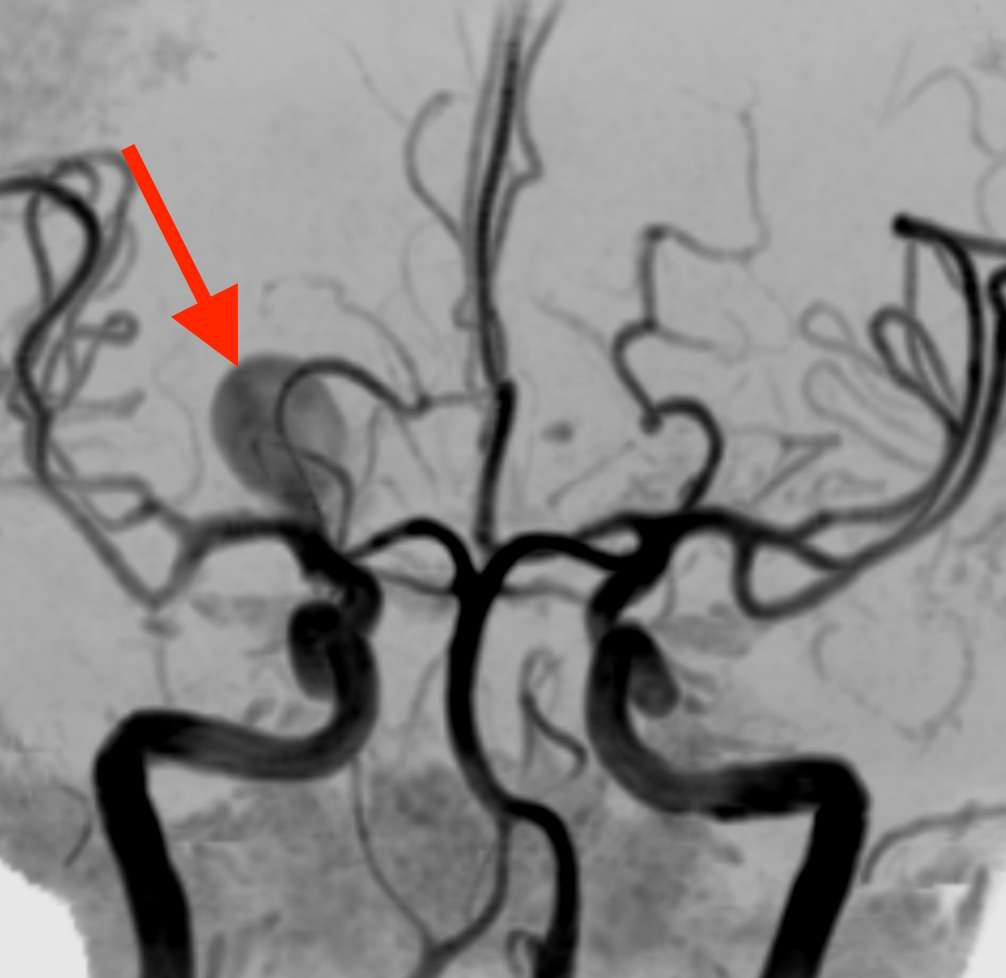

MRAで、右中大脳動脈に直径約5cmの巨大脳動脈瘤が見つかりました。破裂した場合、くも膜下出血を起こす危険があります。

直ちに手術の必要な状態です。そこで、入院のできる病院へ救急搬送していただきました。